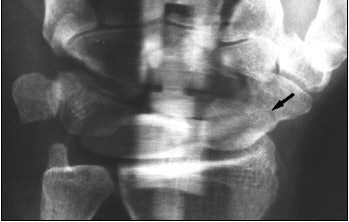

![]() ![]() |

![]() |

| Panoramic radiograph (above) shows fracture line (arrow, fracture type A2). Berná J, Chavarria G, Albaladejo F, Meseguer L, Pellicer A, Sánchez-Cañizares, M, Pérez-Flores, D, "Panoramic Versus Conventional Radiography of Scaphoid Fractures," (AJR, January 2004, Vol.182, pp.155-159) |